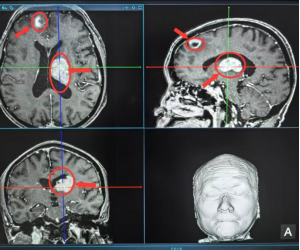

一、病情突发危急,高龄患者陷两难近日,69岁的李先生在家中突发剧烈头痛,被家人紧急送至我院就诊。经头部CT检查,发现其颅内存在一个“慢性硬膜下血肿”——这好比是颅骨与大脑之间一个缓慢扩大的“血包”,如同藏在头内的一颗“定时炸弹”,随时可能因压迫脑组织导致偏瘫、失语甚至昏迷,情况十分危急。(慢性硬膜下血肿示意图)面对这一紧急情况,神经外科团队常规会建议进行“钻孔引流术”,即在头骨上钻一个或两个小孔,将积血引流出来。这虽然是成熟的临床手术,但一听到要在头上“动刀”,李先生和家属满心恐惧,当场表达了抗拒:“医生,我这么大年纪了,实在不想在头上开刀,有没有别的办法?”二、巧用介入新术,精准栓塞破困局面对患者的恳求,我院神经外科团队没有简单地说“不”,而是迅速启动了多学科会诊。结合李先生的年龄、身体状况及诉求,最终提出了一项前沿微创介入方案——脑膜中动脉栓塞术,该技术在国际上已趋于成熟,在国内也逐步